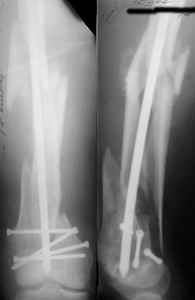

I presented a series of ~25 such cases at EuroTrauma'2004. Many cases were discussed here. I attach am example. Look also recent cases at http://www.hwbf.org/hwb/conf/alex58/scfx.htm,

http://www.hwbf.org/hwb/conf/alex63/alex63.htm

KEMMD> Malpositioning is much too common (recurvatum, varus - valgus).

Did you mark valgus malalignment in that case with LISS you posted Nov 9? Aplication of external distractor can help to avoid the pitfalls but some further development of the technology is necessary to shorten the learning curve.